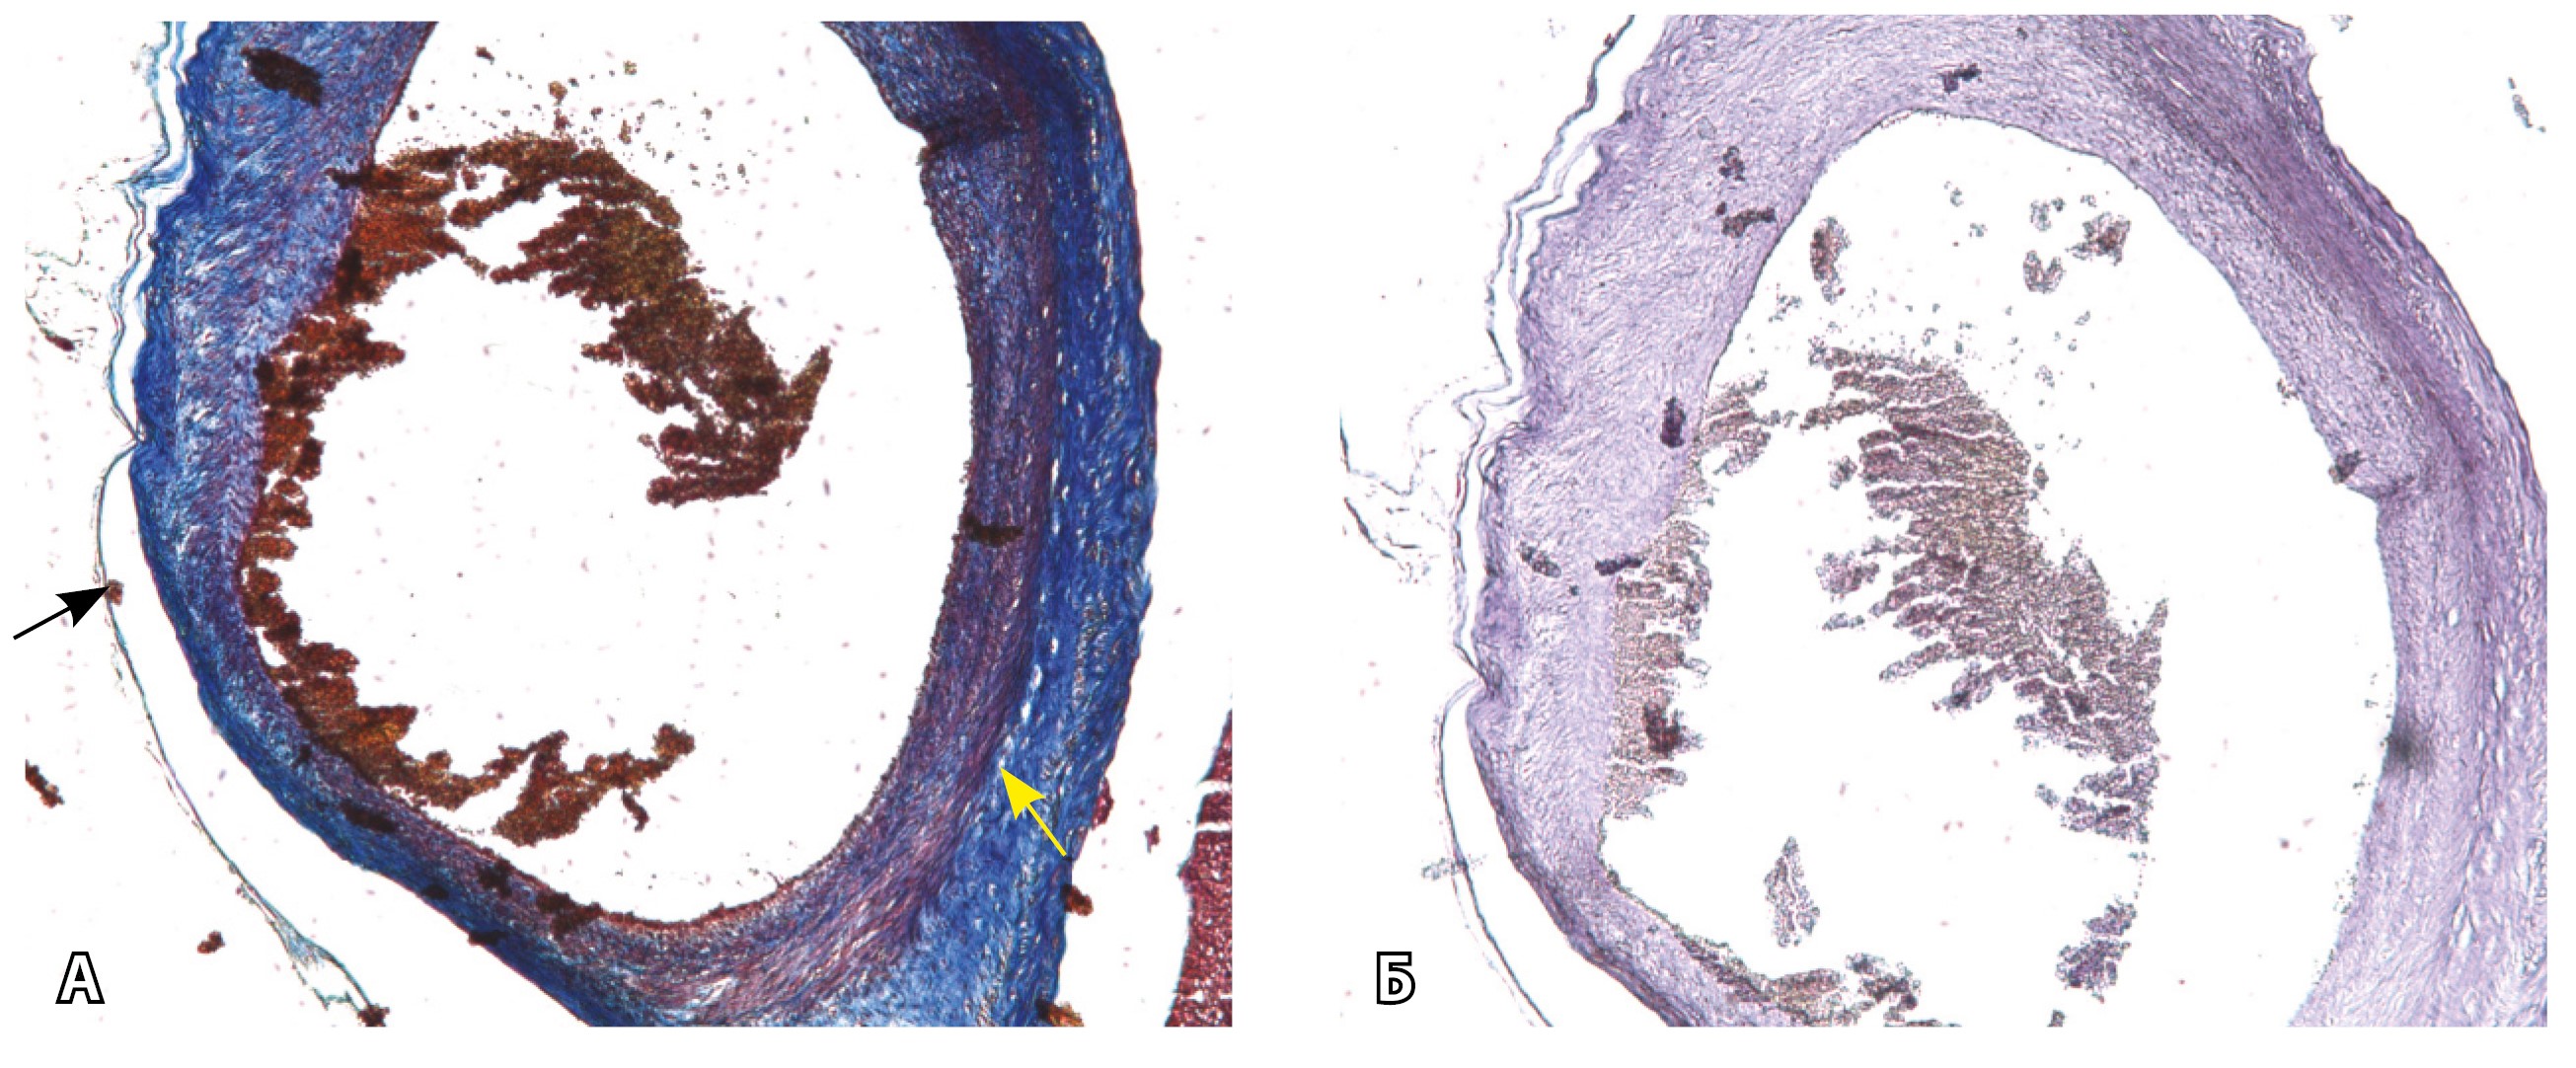

Рис. 13. Самые крупные сосуды в пределах серозной оболочки стенки матки: А, Б – серийные срезы артерии; × 50. При окраске по Маллори (А) видна тонкая полоска мезотелия (черная стрелка), слабо дифференцированная мышечная стенка артерии, вокруг нее – плотная коллагеновая оболочка (желтая стрелка), в просвете определяются тромботические массы. При окраске по Вейгерту (Б) наблюдается полная потеря внутренней и внешней эластических мембран

Эластический каркас представлен сетью тонких волокон, без концентрации на внутреннюю и внешнюю мембраны. Однако маркер СD34 констатирует сохранение эндотелия, что свидетельствует о том, что по артериям циркулирует кровь, не сворачиваясь (рис. 13).

На микропрепаратах васкуляризация серозной оболочки представлена множеством крупных сосудов, идущих в разных направлениях и анастомозирующих друг с другом. Возможно, имеются артериовенозные соустья. На серийных срезах также видно, что в стенках артерий трудно различимы два слоя миоцитов (продольный и поперечный). Со стороны адвентиции они окружены толстым «футляром» из грубоволокнистой голубой ткани (при окраске по Маллори). Она проникает в стенку артерий, замещая мышечный слой (рис. 12).

Главным отличием крупных сосудов в составе серозной оболочки является то, что морфологически они находятся в пределах стенки матки. Об этом свидетельствует наличие в операционном материале тонкого поверхностного слоя мезотелия, отделяющего матку от брюшной полости (рис. 11). Его невозможно визуализировать методом МРТ из-за особенностей метода и толщины получаемых срезов.